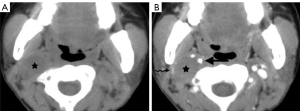

Due to its location between the vein and artery in the carotid space, schwannomas of the vagus nerve tend to separate the artery and vein, usually displacing the CCA/ICA medially and the IJV laterally (Figures 2,3) (12). Some schwannomas of the vagus nerve may displace the IJV and ICA/CCA in a posterior direction without splaying them and there is usually separation between the artery and vein (Figure 4). The cervical sympathetic chain runs in a fascial reflection posterior and slightly medial to the carotid space. Hence, schwannomas of the sympathetic chain tend to displace the IJV and CCA/ICA together, usually anteriorly and laterally (Figure 5) (5). A large schwannoma of the sympathetic chain may distort the surrounding anatomy and result in a posterior displacement of the carotid vessels without separation of the artery and vein (Figure 6) (13,14). Occasionally, a schwannoma of the cervical sympathetic chain may splay the internal and external carotid arteries at the carotid bifurcation but without encasing the arteries (Figure 7) (5). In these regards, the position of the tumor relating to the vessels in the carotid space is more important than the direction of vascular displacement. There has also been a reported case of schwannoma arising from the glossopharyngeal nerve in the carotid space causing posterior displacement of the ICA (15).

In the carotid space, the carotid artery lies centrally and the IJV lies posterolateral to the carotid artery. The cranial nerve X lies in the posterior groove between these vessels, whereas the cranial nerves (IX, XI, XII) pierce the carotid sheath anteriorly just below the skull base. The ansa cervicalis is embedded in the anterior carotid sheath, and the sympathetic chain is found posteriorly (3,4). The deep cervical lymph nodes lie anterior, lateral, and posterior to the IJV (2,5).